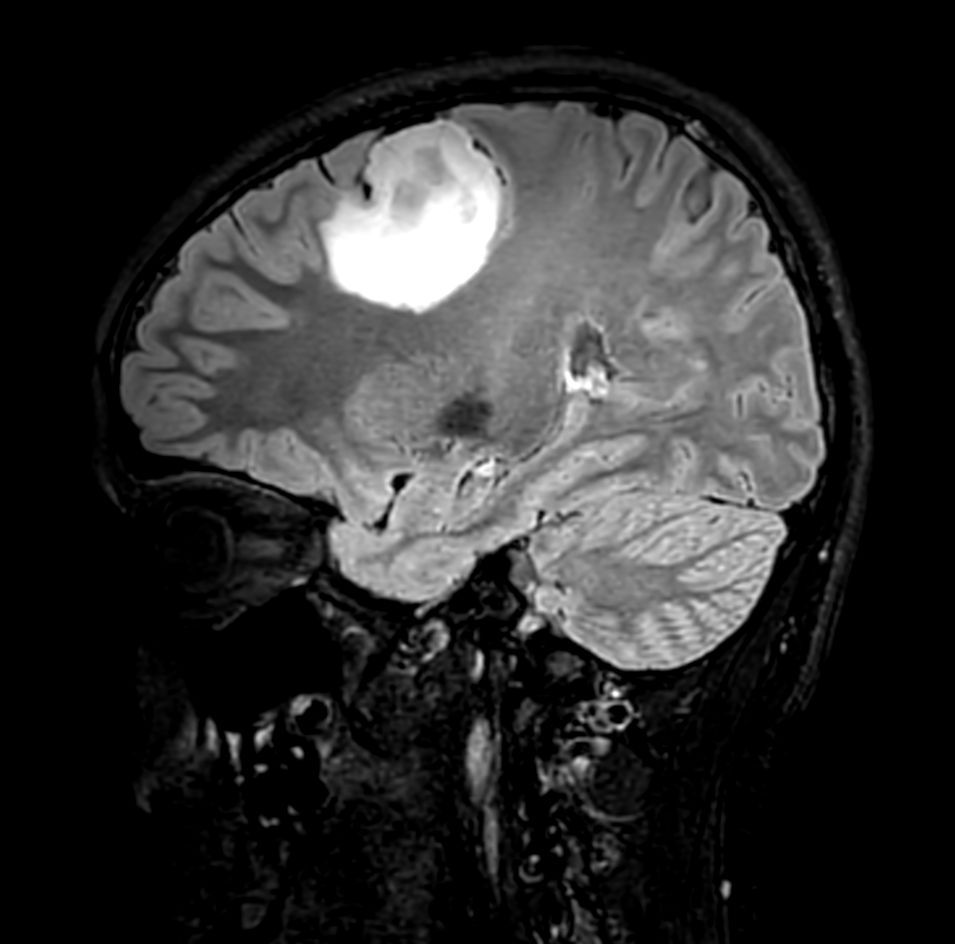

Sagittal 3D T2w FLAIR Compressed SENSE

-

Sagittal 3D T1w TSE +gado Compressed SENSE